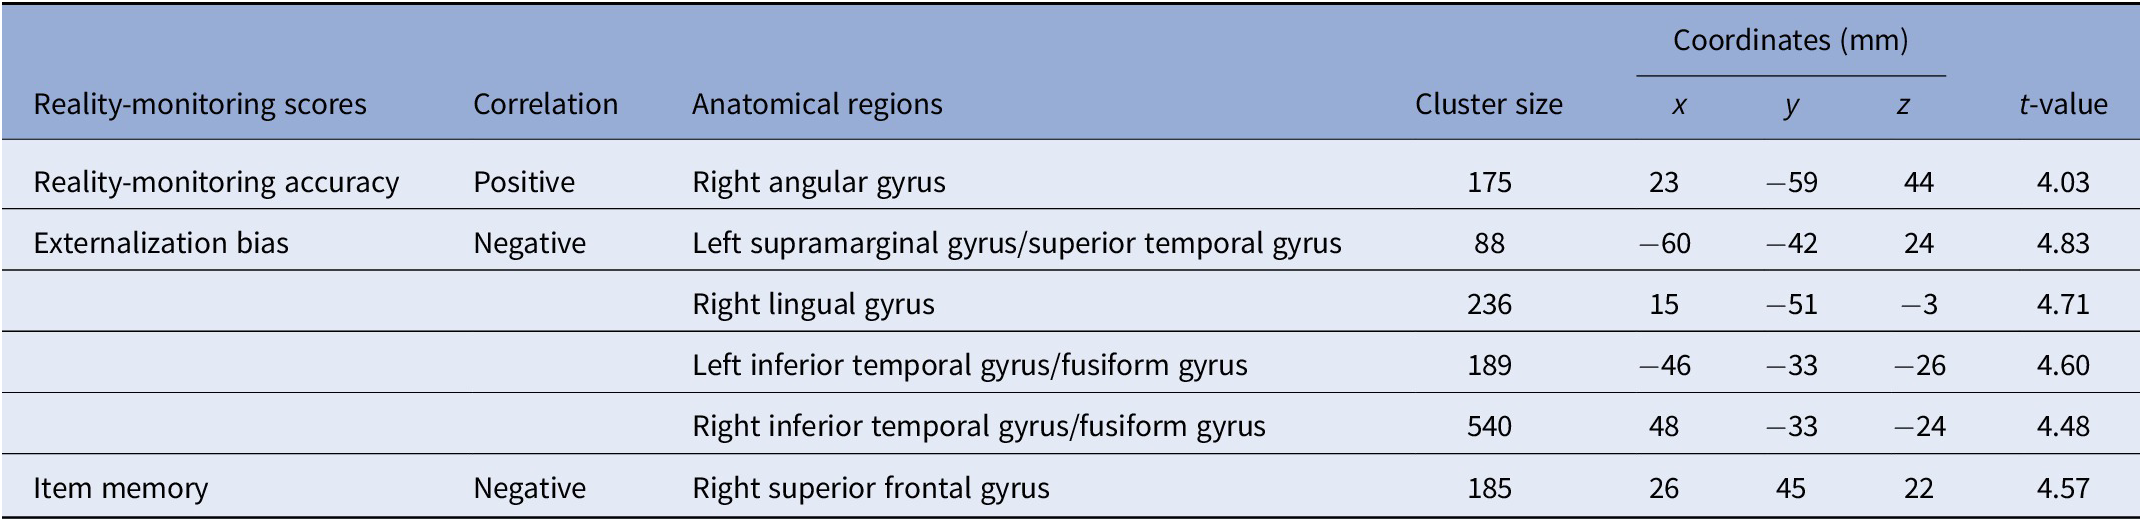

VBM analysis revealed a significant positive correlation between reality-monitoring accuracy and GMV in the right angular gyrus (peak MNI coordinates [23 −59 44], t = 4.03, p < 0.001; see Table 2 and Figure 3A).

Table 2. Clusters showing significant correlations between gray-matter volume and reality-monitoring measures (n = 35).

Note: Statistical threshold of p < 0.001 at the peak-level and FDR-corrected p < 0.05 at the cluster level.

The analysis also revealed a significant negative correlation between the externalization bias and GMV in a cluster encompassing the left supramarginal gyrus and the left superior temporal gyrus ([−60 −42 24], t = 4.83, p < 0.001), in the right lingual gyrus ([15 −51 −3], t = 4.71, p < 0.001), and both in the left and the right inferior temporal gyrus and fusiform gyrus (respectively, [−46 −33 −26], t = 4.60, p < 0.001, and [48 −33 −24], t = 4.48, p < 0.001; Table 2 and Figure 3B).

Additional VBM analyses revealed a significant negative correlation between item memory and GMV in the right superior frontal gyrus (peak MNI coordinates [26 45 22], t = 4.57, p < 0.001; Table 2).